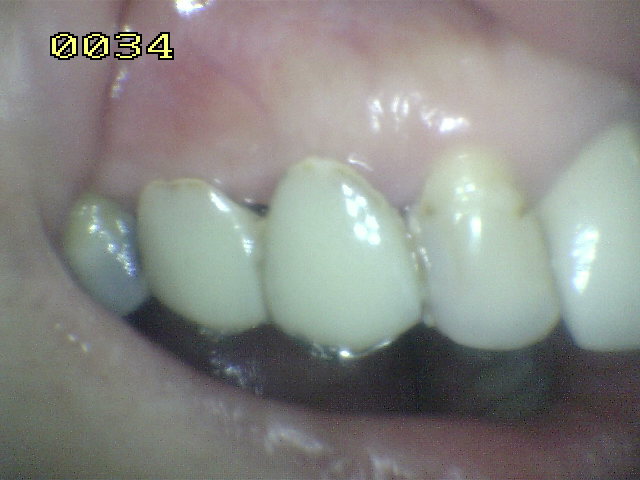

Paciente de sexo femenino de 35 años de edad, que presenta la falta de 23.

Se observa las líneas de extensión metálica del puente Maryland en las piezas talladas.